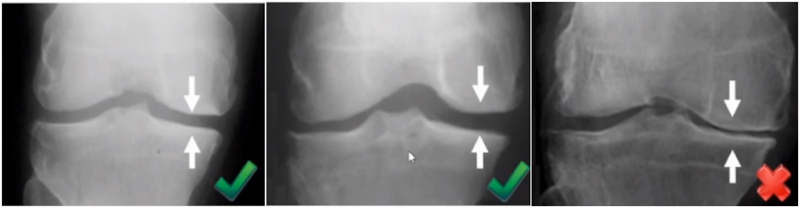

三、单髁置换的适应证——标准侧位片

标准侧位片,内外髁完全重叠,胫骨平台也一样,如果检查不标准,X线片结果会影响判断。

侧位片可以显示胫骨平台磨损部位,在判断前交叉韧带功能是否完好方面有重要意义。当磨损部位在前方或中前方,没有延伸到胫骨平台后缘时,说明前交叉韧带功能正常;当磨损部位延伸到胫骨平台后方,甚至引起后方半脱位状态时,说明前交叉韧带功能缺失或损害,此时不适合做单髁。

AMOA的侧位X线表现

ACL功能完好是单髁重要的适应证。当ACL失去功能,导致后方软骨磨损或者骨缺损,此时为整个内侧或全间室的骨关节炎,不是单髁的适应证了。